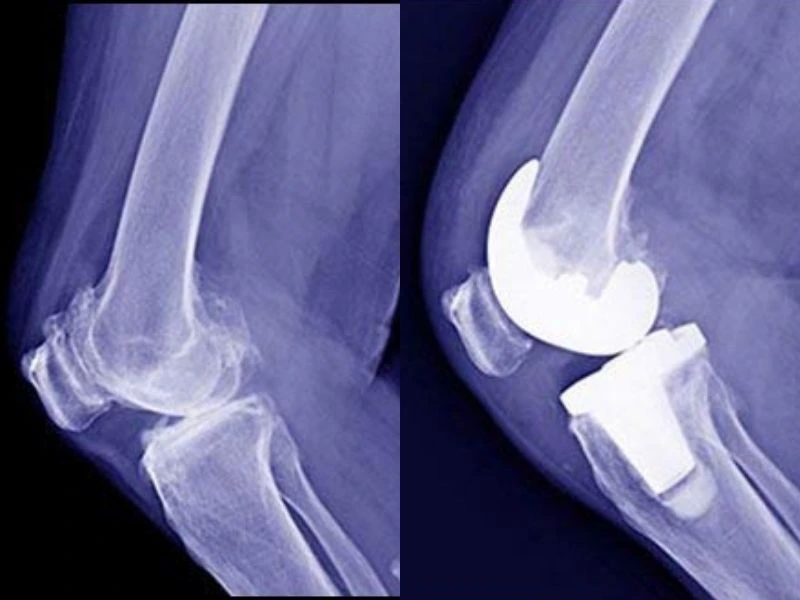

Knee Replacement Mexico

Knee Replacement

Orthopedic surgeries in Mexico are widely preferred by North American patients.

• Mexico: $9,000 – $11,000

• USA: $45,000

• Canada: $18,000 – $22,000